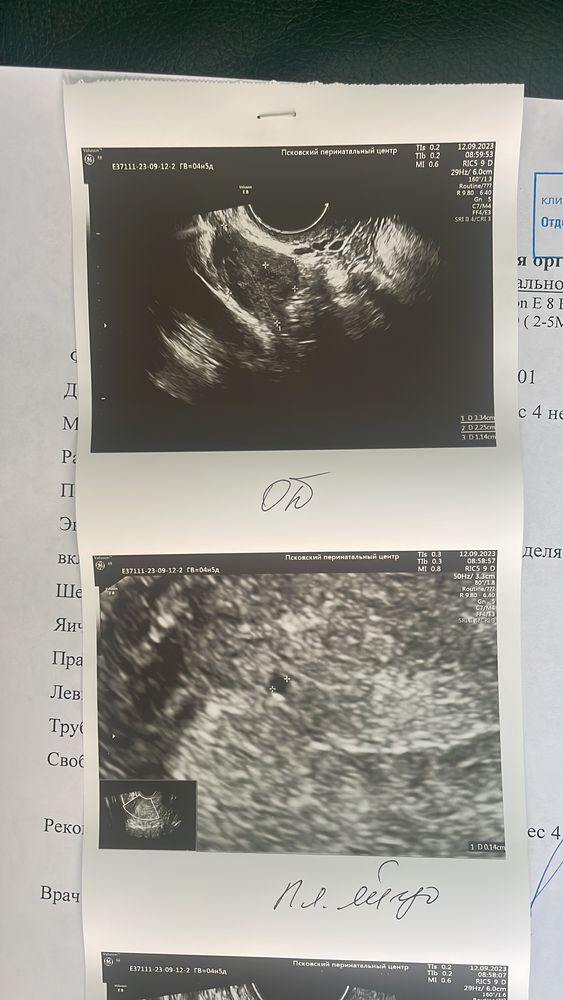

Сделала узи и хгч …

Что-то здесь не то, соглашусь со всеми ниже при таком маленьком хгч невозможно найти ПЯ

Не понимаю, откуда на узи плодное яйцо при хгч чуть больше 100 👀

ПЯ можно увидеть при хгч от 1000-1500

Юлия, у вас хгч 133. При таком значение просто невозможно ничего обнаружить . Сдайте в динамики хгч. Когда будет хгч от 1000 смело идите на узи.

Maria, вы меня успокаиваете 🙏😍 эндометрий 19,5 🫣

Юлия, я была на вашем месте не один раз и знаю, каково вам сейчас.. Скажу одно - настраивайте свои мысли на хорошее.. А эндометрий прямо очень, очень шикарный 🤩 у меня даже такого никогда не было..